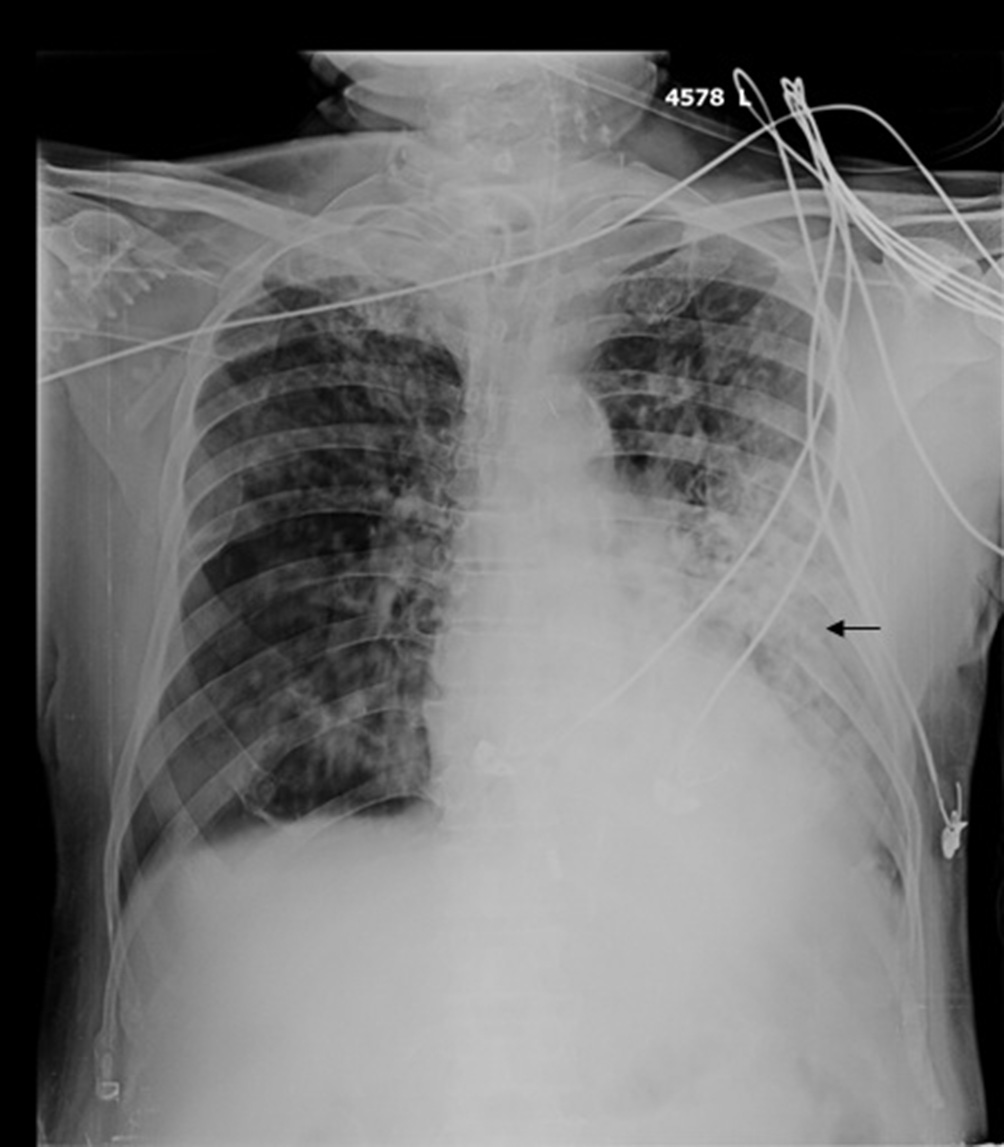

Although HRCT plays an important role in the diagnosis of pulmonary nocardiosis, variations in HRCT findings have not correlated with clinical diagnosis. Here, we describe the radiological features of pulmonary nocardiosis with respect to pulmonary nodules. Impaired cell-mediated immunity would increase the prevalence of infection [6], however, there was no study to examine the status of cumulative and/or daily dose of steroid treatment in patients with pulmonary nocardiosis. Case report: 70 year old patient with history of bronchial asthma presently on treatment with inhaled corticosteroid presented to emergency with complaints of cough with scanty expectoration and increase in breathlessness of 10 days duration. On examination he was tachypneic, tachycardic, had type 1 respiratory failure. Chest auscultation revealed harsh vesicular breath sound with bilateral expiratory wheeze and diminished breath sound in left infra axillary area. Chest x-ray and ultra sound revealed left mid and lower zone consolidation with minimal pleural effusion (Fig. 1). Laboratory evaluation revealed hemoglobin level of 10 g/dL. His WBC count was

Fig. 1. Bilateral nodular radio opacities with large coalescent region in left lower zone (arrow).